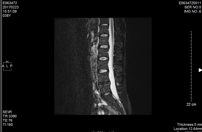

整形外科にてMRI検査では、軽い椎間板ヘルニアと診断される。